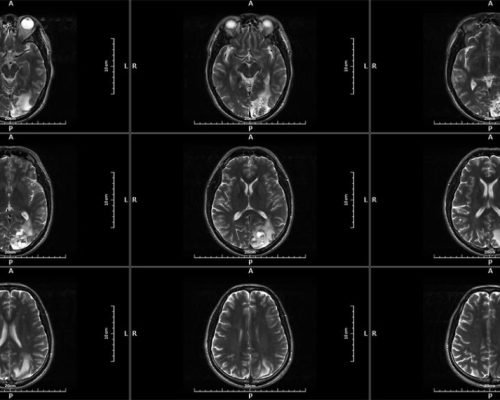

MICA represents the pinnacle of innovation in 1.5T whole-body MRI systems, delivering image quality rivaling 3T systems through its unique High-Temperature Superconducting (HTS) RF coil technology.

MICA is the result of our commitment to develop the world’s highest performing 1.5T whole body MRI system with integrated superconducting RF coil. The superb image quality targeting 3T system performance level is made possible with the unique High-Temperature Superconducing (HTS) RF coils patented by Time Medical Systems.

High-performance gradient system enables faster scanning and sharper images, ideal for advanced neurological and musculoskeletal applications.